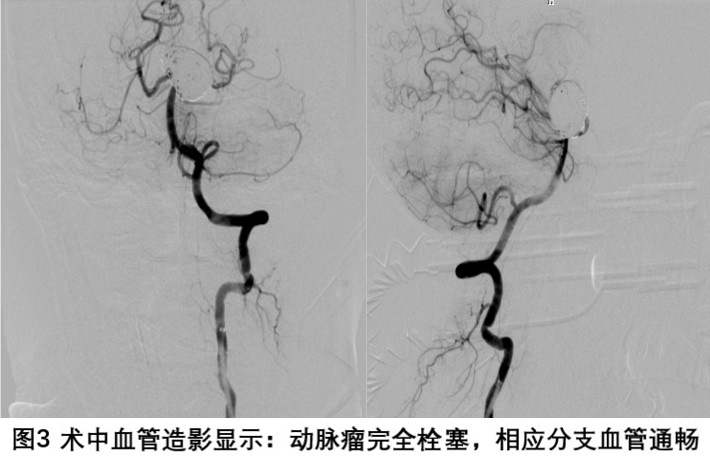

在神经外科王知非主任医师、杨金福主任医师指导下,姜交德副主任医师、卢韶华副主任医师和冯亮医师组成的脑血管病介入治疗手术团队经过周密的术前准备,于3月22日成功给患者实施了Y形支架辅助下基底动脉尖端巨大动脉瘤栓塞术,将这一枚“刀尖上的危险炸弹”拆除。随后,在17病区肖丽护士长带领的护理团队的精心护理下,患者在术后一周左右顺利步行出院。